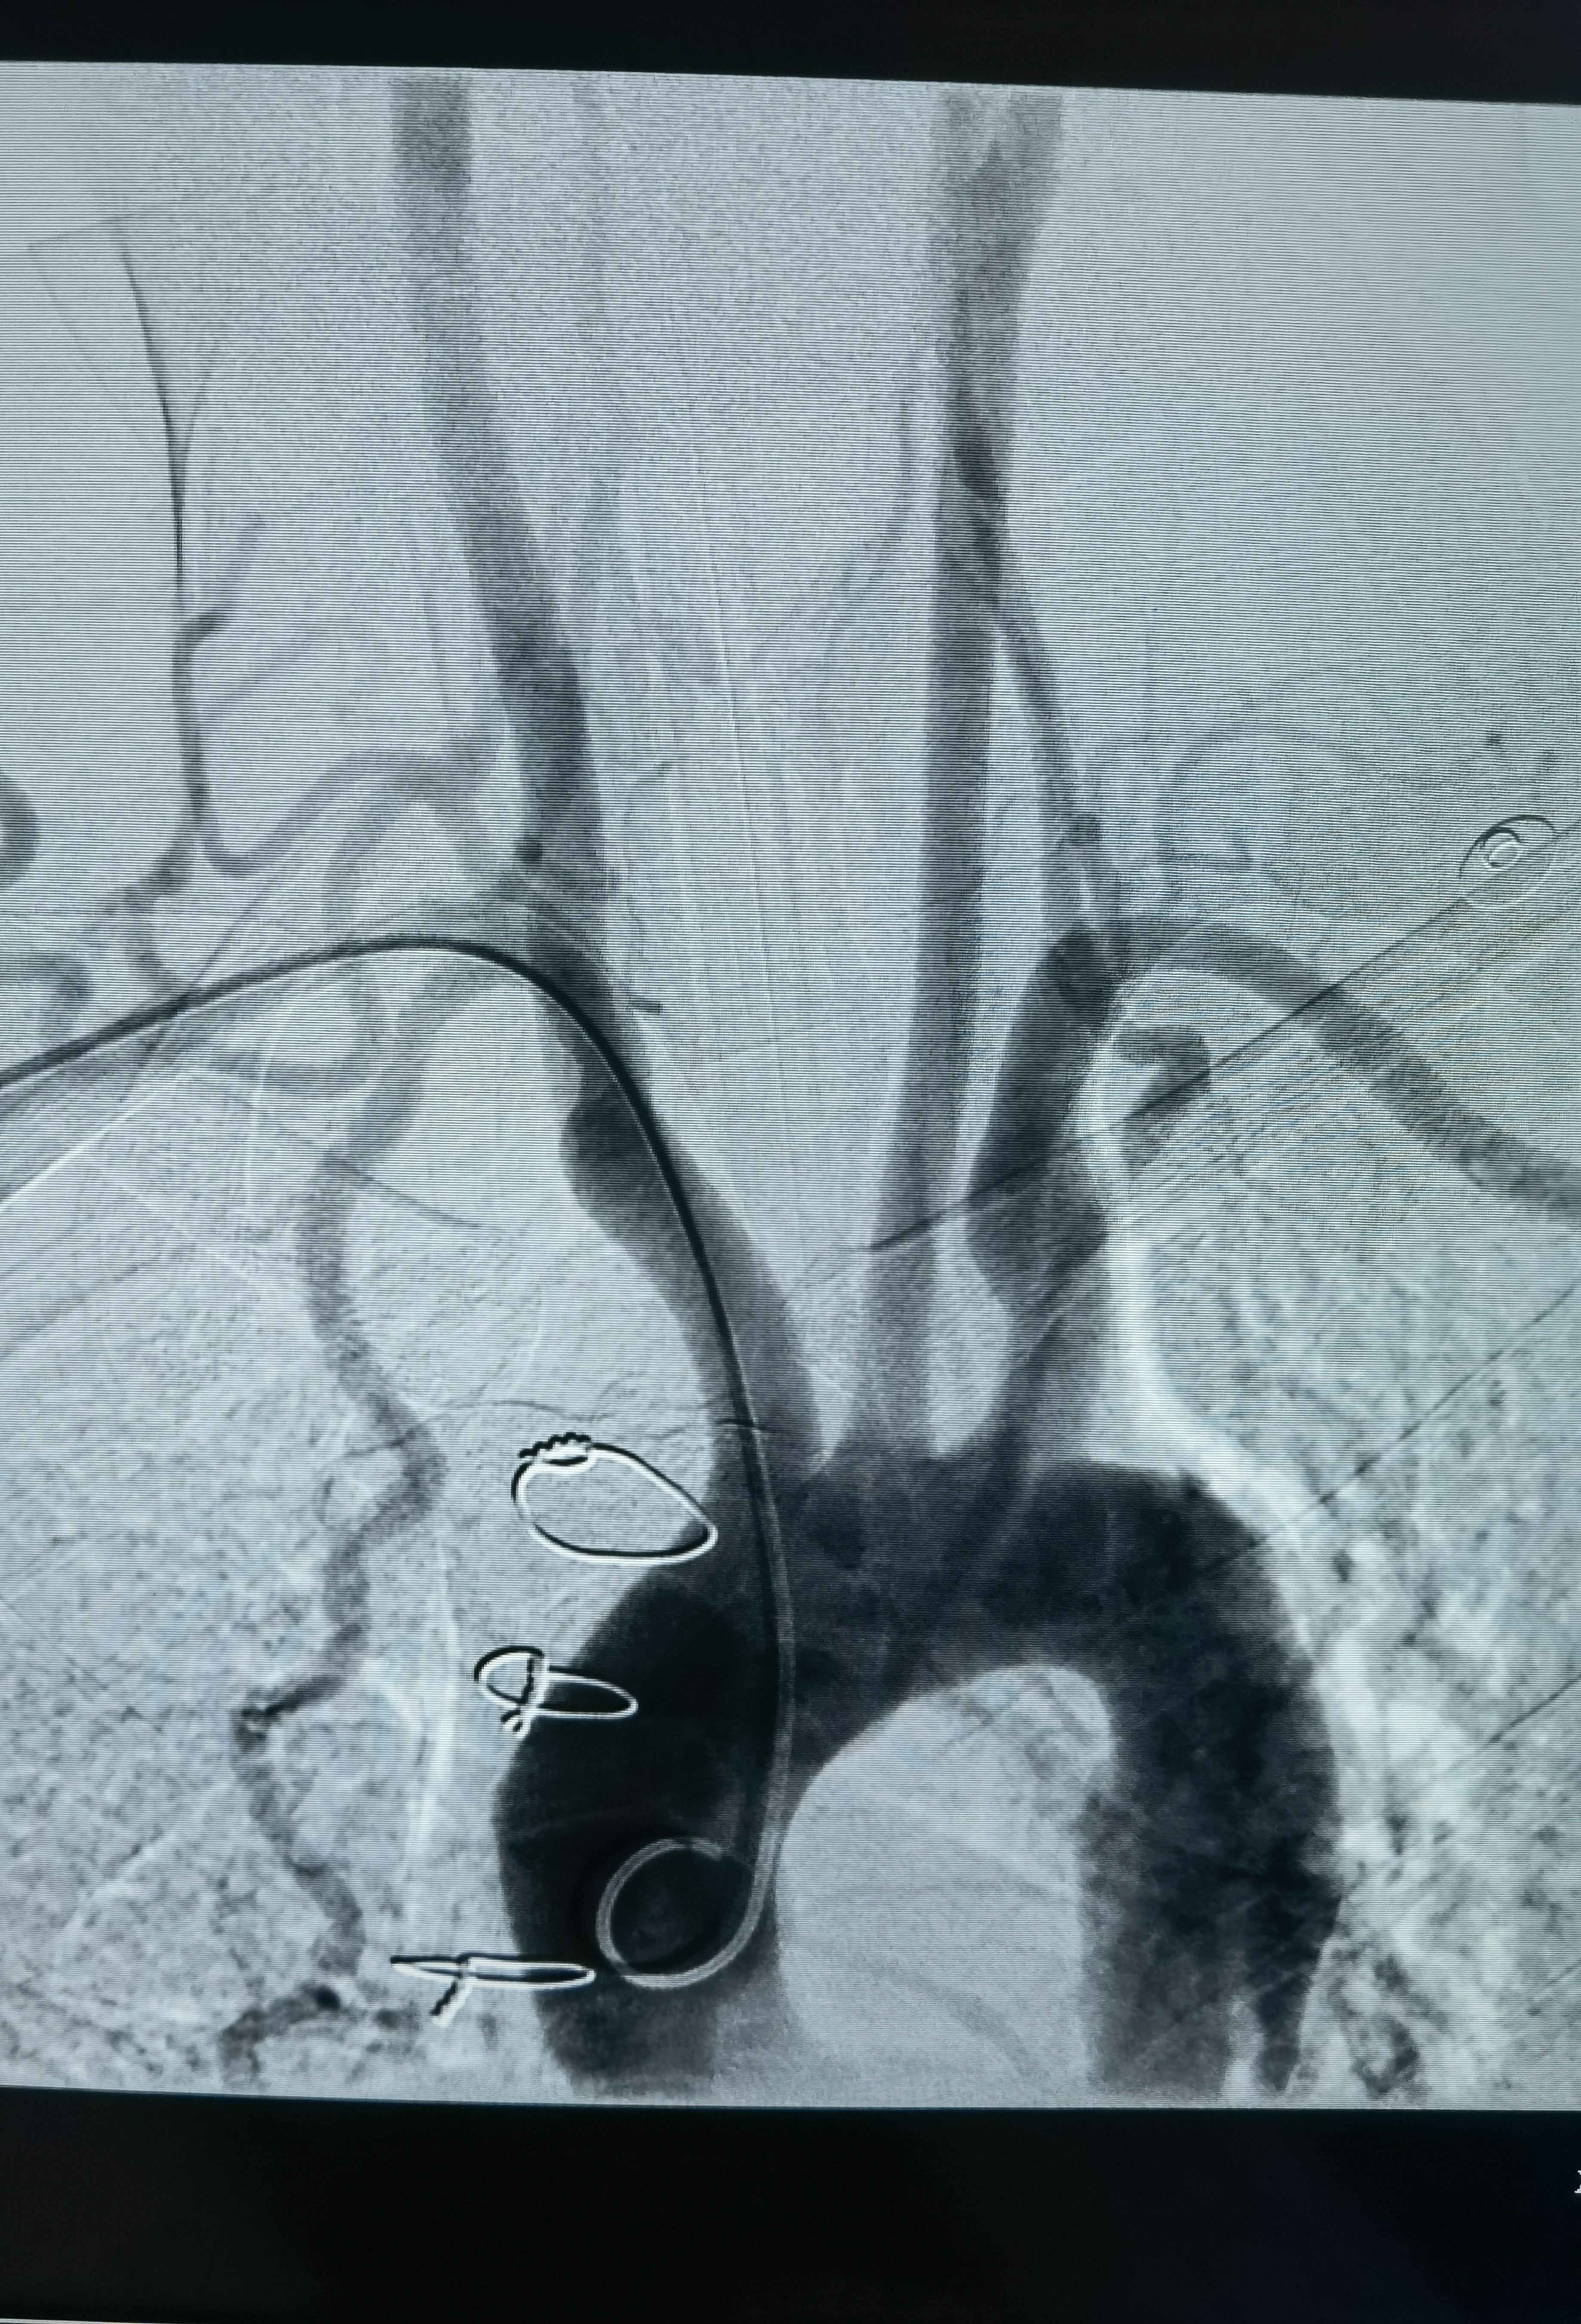

用猪尾巴管再次造影确认腹主动脉确实闭塞了,这时明白为什么股动脉搏动弱不好穿刺了,赶紧换通路,穿刺右桡动脉!可是腹主动脉为什么闭了?紧急请心外科会诊,一打电话心外科说2018年在心外做瓣膜置换术时已经闭了,考虑大动脉炎!

这是术后在影像系统调出来2018年的CTA影像!当时腹主动脉下段已经闭塞了,通过肠系膜上动脉的侧枝以及双侧内乳动脉代偿供血!

改为右桡动脉入路,桡动脉搏动也弱,考虑大动脉炎可能右上肢血管也受影响了,不过还是穿刺成功,泥鳅导丝带猪尾巴管造影,在腋动脉处通过困难,试了两次还是顺利过去了,弓造影上可以看到右侧锁骨下动脉几乎不显影,肋颈干发出粗大分支血管向右上肢供血,说明锁骨下要么闭塞,要么也是重度狭窄,弓造影结束长泥鳅导丝保留,退出猪尾巴管,交换上SIM造影导管,在弓里成袢后超选右颈总困难,导管被血管抱死,导管软,内衬泥鳅导丝推不动!